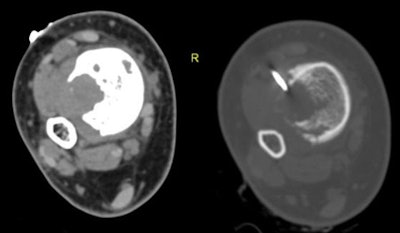

In all, 49 patients including 23 men and 15 women (mean age 33.7 years, range 4-77 years) underwent image-guided biopsies. Imaging in the cohort included radiography, CT, and MRI, and the study team categorized the records according to the location of the host bone, presence or absence of an extraosseous soft-tissue component (usually at MRI), and imaging nature of the lesion matrix (usually at CT) including lytic, sclerotic, or mixed lytic and sclerotic.

Cross-sectional imaging showed an extraosseous component in about half (26/49) patients, which facilitated biopsy and obviated the need for cortical breach, the authors wrote. The other 23 patients had completely intraosseous lesions that required more aggressive efforts to reach the lesion, the study team wrote.

Based on imaging findings at CT and x-ray, initial diagnostic yield was higher for mixed lesions (94%), followed by sclerotic (89%) and lytic (83%) lesions, according to the authors. As for the completely intraosseous lesions, the diagnostic yield was 74%, while the presence of extraosseous soft-tissue components raised the diagnostic yield to 100% in 26 cases.

"The image-guided percutaneous biopsy has proved to be a safe, minimally invasive, and cost-effective procedure for the diagnosis of skeletal lesions, obviating the need for the more risky and invasive open surgical biopsy in most patients, wrote Nouh and Abu Shady. "Meticulous technique regarding compartmental barriers, neurovascular structures, and seeding of malignant cells along the biopsy needle track are prerequisites for optimized treatment strategies with limb-salvage procedures. CT has proven to be a recognized modality for guiding PCNB of deep-seated musculoskeletal lesions."

The lesion matrix, as visualized on the different imaging modalities, is a major factor determining the biopsy instrumentation choice and percutaneous biopsy decision, the authors wrote. In line with previous studies, the study reached higher diagnostic yields for lesions of mixed matrices, followed by sclerotic lesions and lytic lesions.